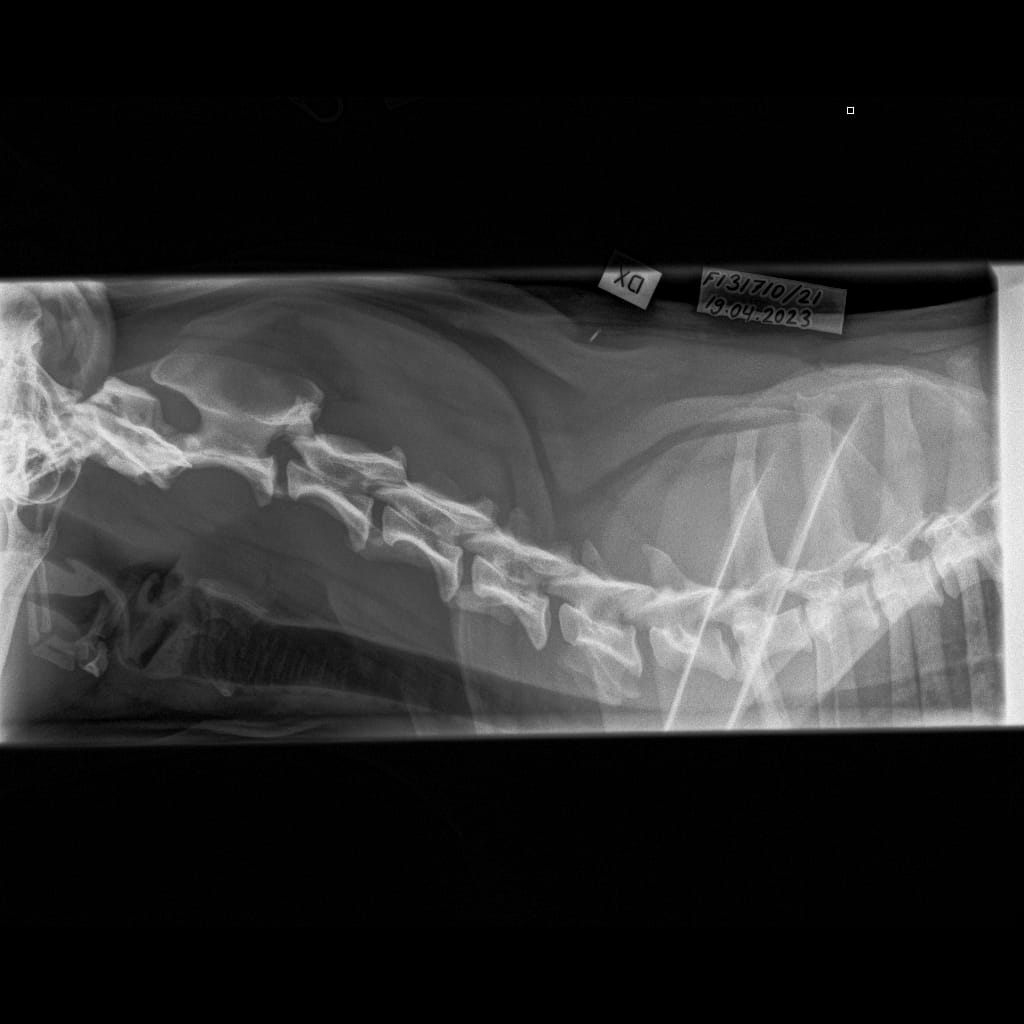

| Name | ID | Birth weigth | Ridge | Height | Weight | Bite | Hips | Elbows | Shoulders | Spine | MH | Other |

|---|---|---|---|---|---|---|---|---|---|---|---|---|

| Lumottu Uljas Iivonpoika ft. Finnridge | Blue ♂︎ | 505 g | Correct | TBA | TBA | TBA | B/B | 0/0 | Unaffected/Unaffected | LTV1, SP0, VA1 | MH, gunshot proof | Low-grade MCT removed 06/2024 |

| Lumottu Aatos Iivonpoika ft. Finnridge | Turqoise ♂︎ | 530 g | Correct | TBA | TBA | TBA | B/B | 0/0 | Unaffected/Unaffected | LTV2, SP0, VA0 | MH, gunshot proof | |

| Lumottu Martta Iivontytär ft. Finnridge | Lime ♀︎ | 525 g | Correct | TBA | TBA | TBA | A/A | Xray: 0/0 CT: 3/1 | Unaffected/Open to interpretation | LTV0, SP0, VA0 | MH, unfamiliar to gunshot | |

| Lumottu Armas Iivonpoika ft. Finnridge | Orange ♂︎ | 440 g | Correct | TBA | TBA | TBA | A/A | 0/0 | Unaffected/Unaffected | LTV0, SP0, VA0 | MH, unfamiliar to gunshot | |

| Lumottu Aulis Iivonpoika ft. Finnridge | Aqua ♂︎ | 440 g | Correct | TBA | TBA | TBA | B/B | 1/1 | Unaffected/Unaffected | LTV1, SP0, VA0 | Handler interrupted | |

| Lumottu Irma Iivontytär ft. Finnridge | Pink ♀︎ | 550 g | Correct | TBA | TBA | TBA | C/B (low sockets) | 0/0 | Unaffected/Unaffected | LTV0, SP0, VA0 | Spring 2024 | |

| Lumottu Sirkka Iivontytär ft. Finnridge | No collar ♀︎ | 390 g | Ridgeless | TBA | TBA | TBA | A/A | 0/0 | Unaffected/Unaffected | LTV1, SP0, VA0 |